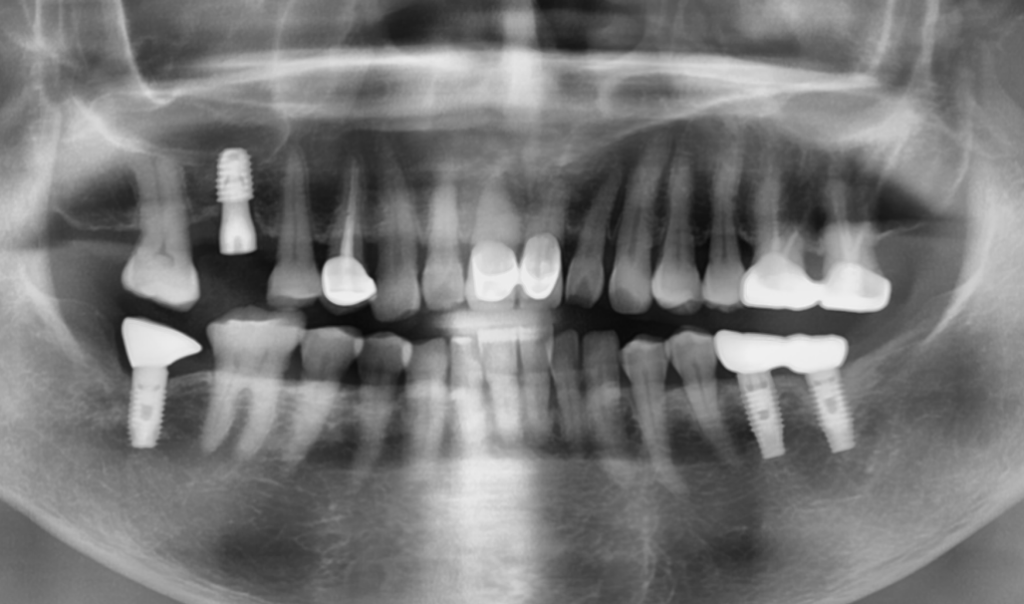

23. 02. 24(임플란트 뿌리 부분 주변으로 번져있는 염증)

혹시 빨간색 표시한 부위의 염증이 엑스레이에서 보이시나요? 임플란트의 나사선을 타고…잇몸뼈가 검게 바뀌어 있는 부분 말입니다. 엑스레이는 2D 영상이기에 바깥쪽과 안쪽이 중첩되어 염증의 소견이 전문가의 눈에서만 보입니다.

위의 경우 엑스레이 상으로 이정도의 수직적 골파괴가 확인 되었다면 조금 더 확실한 확인을 위해 컴퓨터 단층 촬영 CT를 해보게 됩니다.